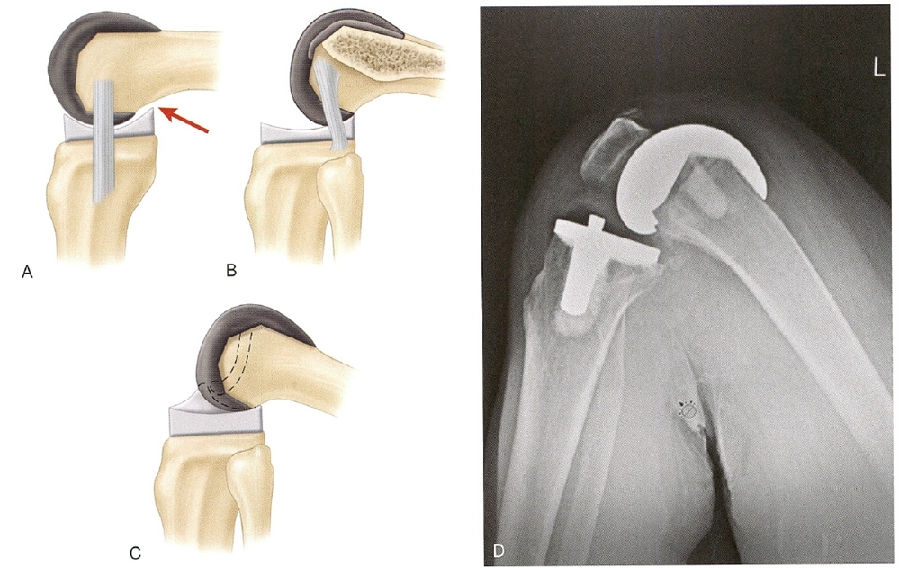

在保留后交叉韧带的情况下,股骨的后滚现象是通过膝关节屈曲过程中由于PCL的张力来完成的(图4PCL过度紧张会导致术后屈曲角度下降或者过度的股骨后滚,可能会加快聚乙烯的磨损。相反,若PCL在屈曲过程中没有足够的张力,股骨后滚现象就无法实现。为了获得PCL保留型假体的最佳功能和寿命,必须精确地平衡PCL

4 A.随着后髁偏距的丧失和股骨假体在胫骨上的前滚,股骨后部和聚乙烯衬垫撞击导致屈曲受限。B.适当的股骨后髁的偏距和功能正常的后交叉韧带(PCL),可以优化屈曲,而不会使股骨后部撞击胫骨衬垫。C.带有立柱和凸轮的后稳定假体可驱动胫骨托上的股骨假体后滚,优化屈曲。D.X线片为后稳定TKA的一个例子,显示出最佳屈曲后髁得到完全支撑,聚乙烯后唇没有边缘负荷